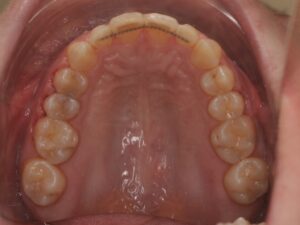

- d’un fil collé sur la face interne (linguale) des dents

- de gouttières passives de stabilisation réalisées sur mesure. `